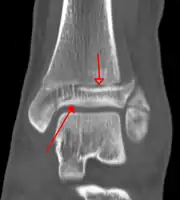

X-ray

On X-rays, there can be a fracture of the medial malleolus, the lateral malleolus, or of the anterior/posterior margin of the distal tibia. [17] If both the lateral and medial malleoli are broken, this is called a bimalleolar fracture[18]. If the posterior malleolus is also fractured, this is called a trimalleolar fracture. [19]

A triplane fracture of the ankle as seen on CT